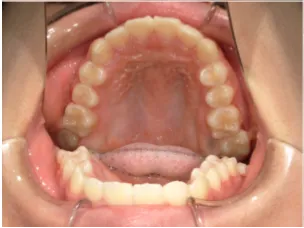

治療中④小2(8y2m)~小3(9y1m):QHとBHで拡大・アーチ形態の修正、ブラケットで前歯の並べ替えまで終了

治療中⑤小3(9y2m):モノブロック装置(筋機能的咬合誘導装置)で永久歯の咬み合わせ治療へ移行

| 行ったご提案・診断内容 | 成長期に行う治療と咬合治療をご提案 受け口用ファンクショナルアプライアンス(写真②③)からスタートし、小2以降で上下顎の拡大・歯列弓の形態修正・前歯の並べ直し(写真④)を行いその後、モノブロック(筋機能的咬合誘導)装置(写真⑤)へ移行し、受け口の再発予防と永久歯を適切な咬み合わせに誘導し、必要によりマルチブラケット法へ移行する治療方法を提案しました。 成長期治療(成長時期にお口の環境を整える治療) 2年生以降から 咬合治療 |